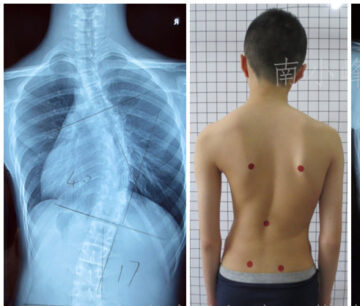

علاج اعوجاج العمود الفقري في مركز الرواد يُعَدّ اعوجاج العمود الفقري من أكثر مشكلات العظام شيوعًا بين الأطفال والمراهقين، وقد يظهر أحيانًا عند البالغين أيضًا. وهو عبارة عن انحناء جانبي غير طبيعي في العمود